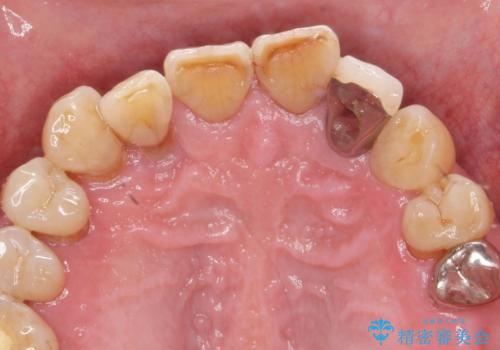

セラミック治療を行う前に歯周病の問題を解決すべく歯周外科を行い歯周ポケットを除去し整備したのちセラミックブリッジ・クラウンの製作を行います。

歯周外科を行ったことで非常に安定した歯周環境となり、引き締まった歯ぐきとなりました。